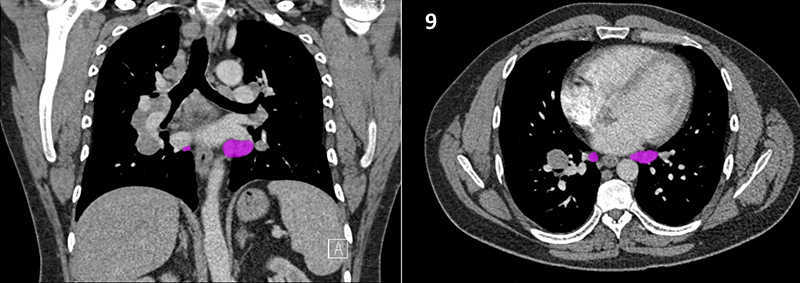

Nodal zones and stations according to the International Association for the Study of Lung Cancer (IASLC) node map.

Table (above): Nodal zones and stations according to the International Association for the Study of Lung Cancer (IASLC) node map. (Source: 1,2) *Depends on the side of the tumour.